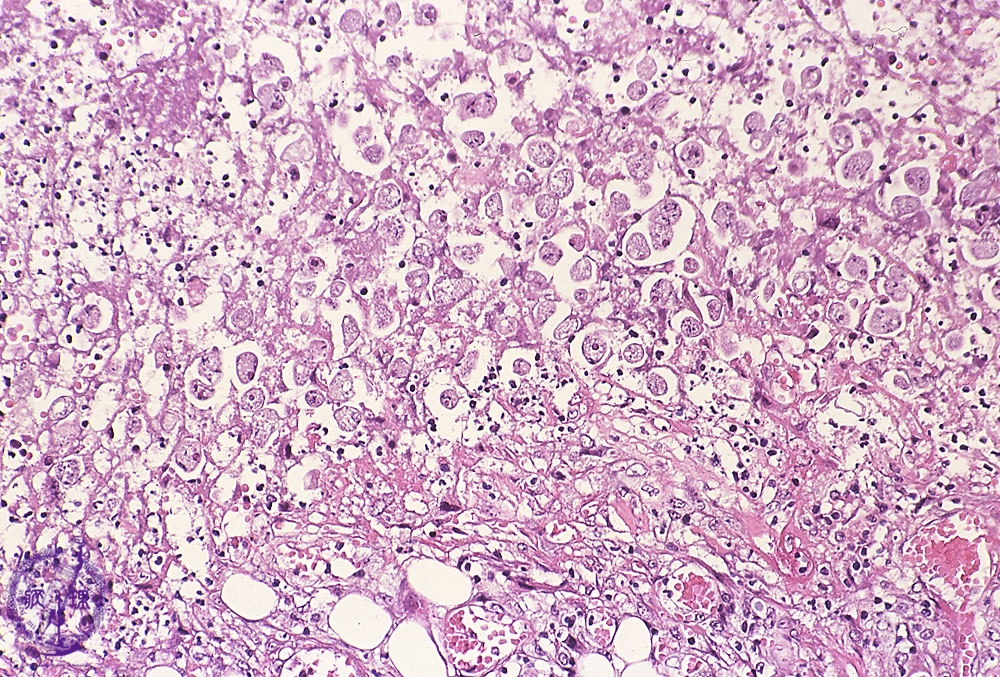

Microscopic view (H&E stain, high power): Many amoeba trophozoites are seen forming cysts.